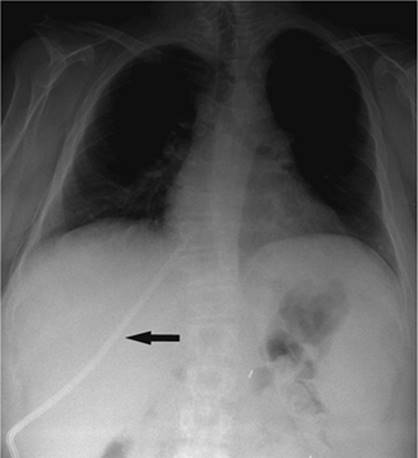

If a pneumothorax occurs in association with thoracic intervention, or secondary to underlying lung disease, a chest tube/pleural catheter may be required. The indications for tube placement include size of pneumothorax greater than 25%, pain, shortness of breath, or progressive enlargement on serial radiography. These tubes are easily placed in the second or third intercostal space anteriorly. Our preference is to place an 8 French catheter under fluoroscopic guidance using the Seldinger technique to avoid injury to the adjacent lung. We gain access with a 4 French micropuncture system (Angio Dynamics, Queensbury, NY) followed by insertion of a 0.035 guidewire over which the chest tube is advanced. This is secured in place with nonabsorbable suture and covered with petroleum jelly gauze to decrease the risk of air leak. Most of the pneumothorax is aspirated using a 60-mL syringe with the aid of a three-way stopcock. Then the tube is connected to a Pleur-Evac drainage system as is done with surgically placed chest tubes. The pleural catheter remains in place until there is no significant residual pneumothorax and there is no evidence of air leak when the tube is connected to water seal (Fig. 35.7A–C).

000415

Figure 35.7. A 70-year-old female with progressive pneumothorax following placement of transvenous cardiac pacing device. A: Arrows indicate the partially collapsed left lung following pacing device placement. B: Fluoroscopic image obtained at time of 8 Fr chest tube insertion. The tube was placed slightly lower than the usual apical position to avoid potential damage to the pacing device or wires. C: Following chest tube insertion, the pneumothorax was evacuated with syringe aspiration of the air. Follow-up chest radiograph demonstrates near-completed resolution. The chest tube was connected to Pleur-Evac drainage system.